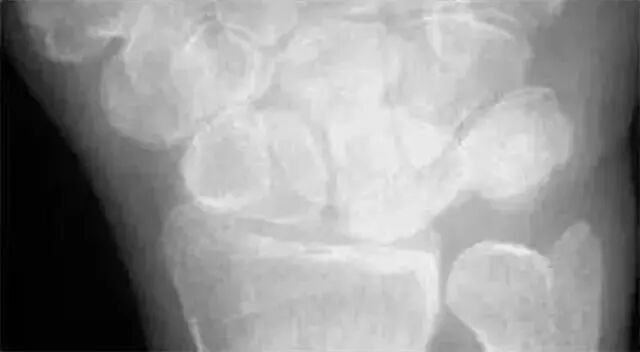

看是否有骨折:主要以舟骨、月骨常见,其他腕骨骨折一般较少,侧位注意不要漏诊三角骨即可;看桡骨远端不要漏诊关节面和纵行小梁的骨折。

两条弧线 如果不连通 多半有脱位

我们把月骨看做是香蕉,把头状骨看做是苹果。香蕉下面的桡骨关节面是盘子,盘子上面有香蕉,香蕉上放个苹果,苹果被咬了一口,在前面是三角骨骨折。香蕉歪了是月骨脱位,苹果向后是月骨周围脱位。

若显示腕骨弧线不连续或各弧线不平行,或腕掌线M形结构消失,应高度怀疑腕关节不稳或脱位。

Analyze-腕骨弧线正位弧线不连续,侧位明显脱位。